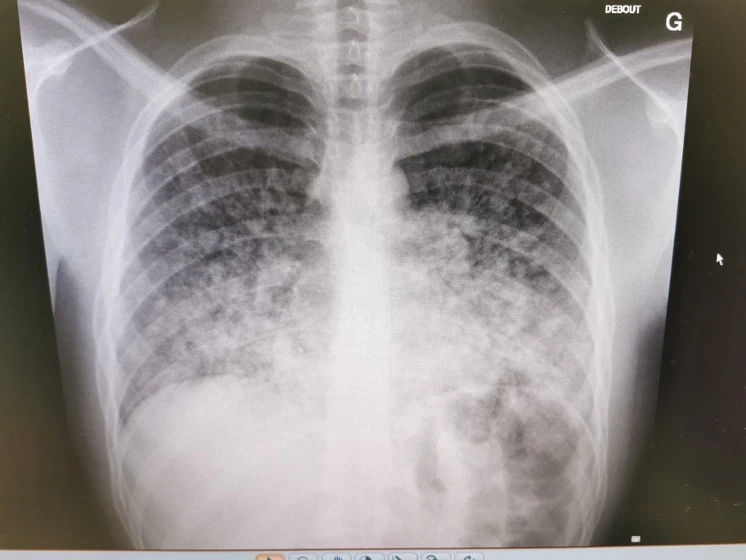

Radiographie du thorax :

L’image ci-dessus est une radiographie debout, antéro-postérieure d’un jeune patient se présentant avec une dyspnée et une hémoptysie. La radiographie démontre un infiltrat alvéolaire diffus, prédominant aux deux bases, signant d’une hémorragie alvéolaire.